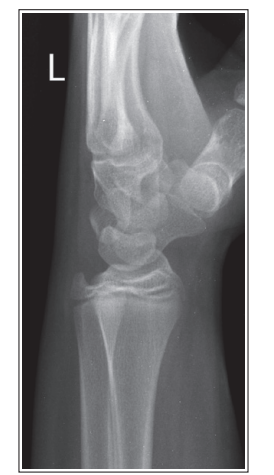

What is wrong with this oblique wrist xray

Under-rotated

Less than 45 degree obliquity